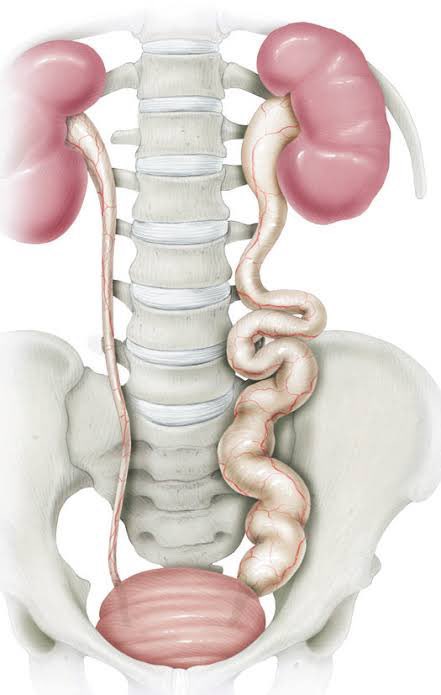

En pacientes con doble sistema colector completo, la LEY DE 𝗪𝗘𝗜𝗚𝗘𝗥𝗧-𝗠𝗘𝗬𝗘𝗥 establece que el uréter que drena el polo superior del riñón se inserta medial y distal (inferior) al sitio de inserción del uréter que drena el polo inferior📚📝 #SoMe4PedSurg #UroSoMe #UroPed